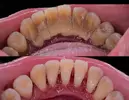

نزيف اللثة

أمراض الأسنان واللثة